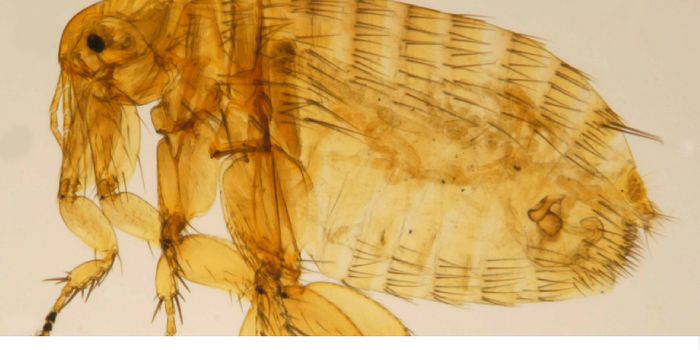

JUN 27, 2017Clinical & Molecular DXThe bloodsucking parasites that carry Lyme disease may also be the key to new anti-inflammatory drugs that could prevent ...

JUN 29, 2017Clinical & Molecular DXIf you thought the plague has been eradicated, think again. This year, the New Mexico Department of Health (NMDOH) alrea ...